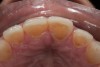

Fig 14. Postoperative view showing additively restored palatal surfaces of upper anteriors.

Figure 14

A few weeks later, the facial veneers were bonded directly to the underlying enamel. A postoperative photograph (Figure 11) revealed the restored harmony of the patient’s smile and the occlusal contacts in MIP (Figure 12). The palatal surfaces restored with nanofilled composite resin developed good anterior guidance that was harmonized to the patient’s chewing cycle (Figure 13 and Figure 14).19